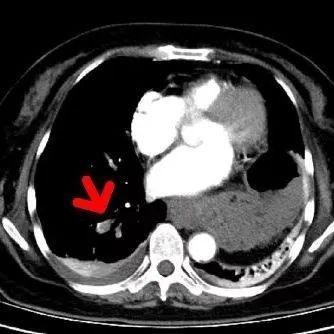

术后复查造影可见右肺动脉血栓消失,

轮廓正常,管腔也粗了

该病例的

复查随访

可见原有的大块血栓完全消失